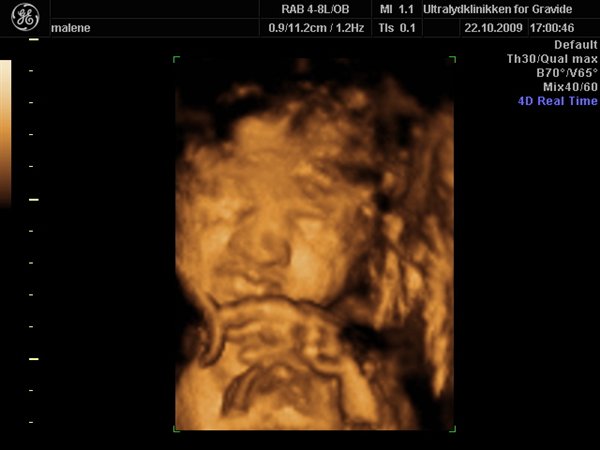

Jeg havde egentlig besluttet fra start af at jeg ville bestemt ikke smide penge efter en 3D scanning, men må indrømme jeg blev fristet

Så vi fik en hurtig tid i eftermiddags, og kom op og vinke lidt til den lille meget stædige prinsesse som vi så fint bekræftet hun er

Hun har allerede nu en masse hår på hovedet, og ligger meget dybt i bækkenet, så det var ikke muligt at få hele hovedet med, da man jo ikke kan scanne igennem knogler.

Hun var lige som hun skulle være, og vejer 1200 g

Vedhæftede fotos (klik for at se i fuld størrelse)